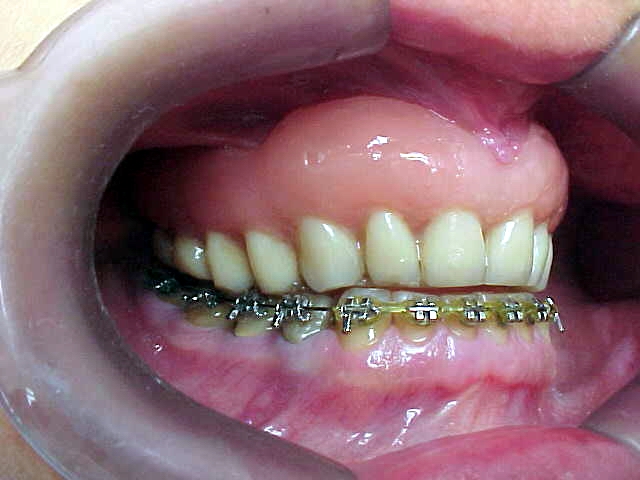

Aumento posterior para facilitar mecânica ortodôntica no arco inferior

Aparelho ortodôntico instalado